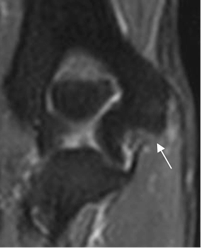

Fig 45 A. Ruptura del LCM.

RM coronal en STIR. Solución de continuidad, sobre el origen humeral de la banda anterior del LCM.